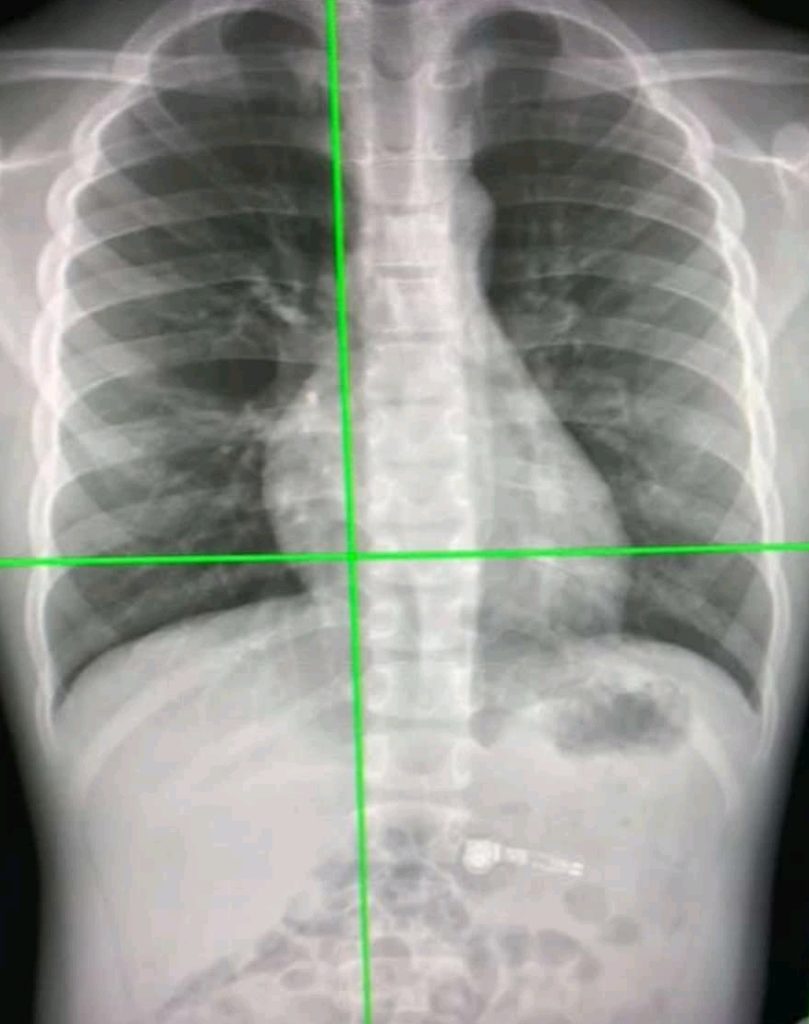

Tokyo, Aug 18 (IANS) Japanese scientists have developed an advanced artificial intelligence (AI) model that utilises chest radiographs to accurately estimate a patient’s chronological age.

The team from Osaka Metropolitan University first constructed a deep learning-based AI model to estimate age from chest radiographs of healthy individuals. They then applied the model to radiographs of patients with known diseases to analyse the relationship between AI-estimated age and each disease.

The developed model showed a correlation coefficient of 0.95 between the AI-estimated age and chronological age. Generally, a correlation coefficient of 0.9 or higher is considered to be very strong.

The results revealed that the difference between AI-estimated age and the patient’s chronological age was positively correlated with a variety of chronic diseases, such as hypertension, hyperuricemia, and chronic obstructive pulmonary disease. In other words, the higher the AI-estimated age compared to the chronological age, the more likely individuals were to have these diseases.